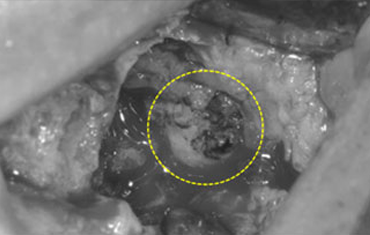

타 치과의 뼈 이식 후 골조직

램브란트치과 상인점 뼈이식 후 골조직